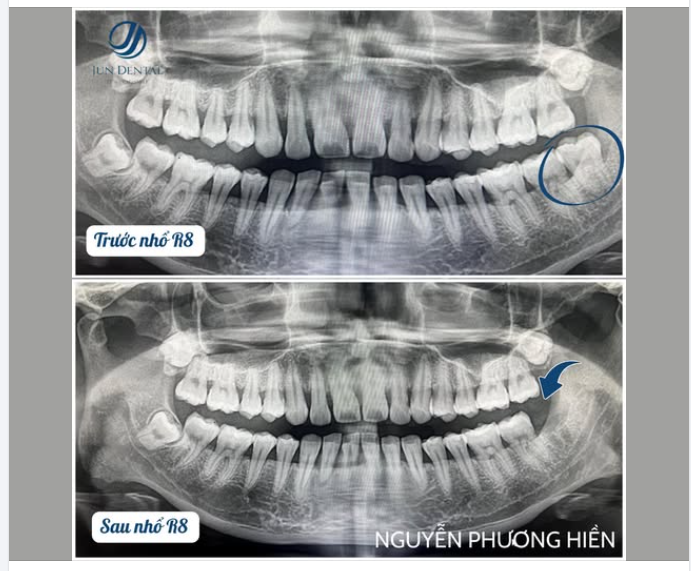

CA LÂM SÀNG: NHỔ RĂNG KHÔN R48 LẬP KẾ HOẠCH CẤY IMPLANT R36 KHÁCH HÀNG PHẠM NGỌC HỒNG VY – JUNDENTAL